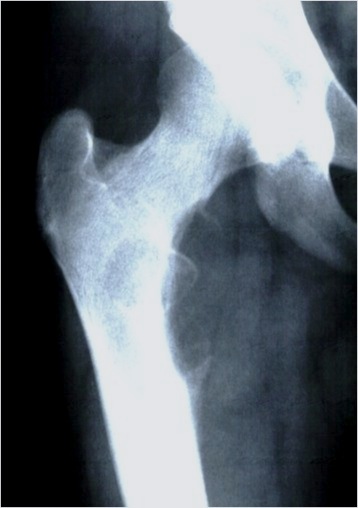

Ewing's acomion Ewings lesser trochanter